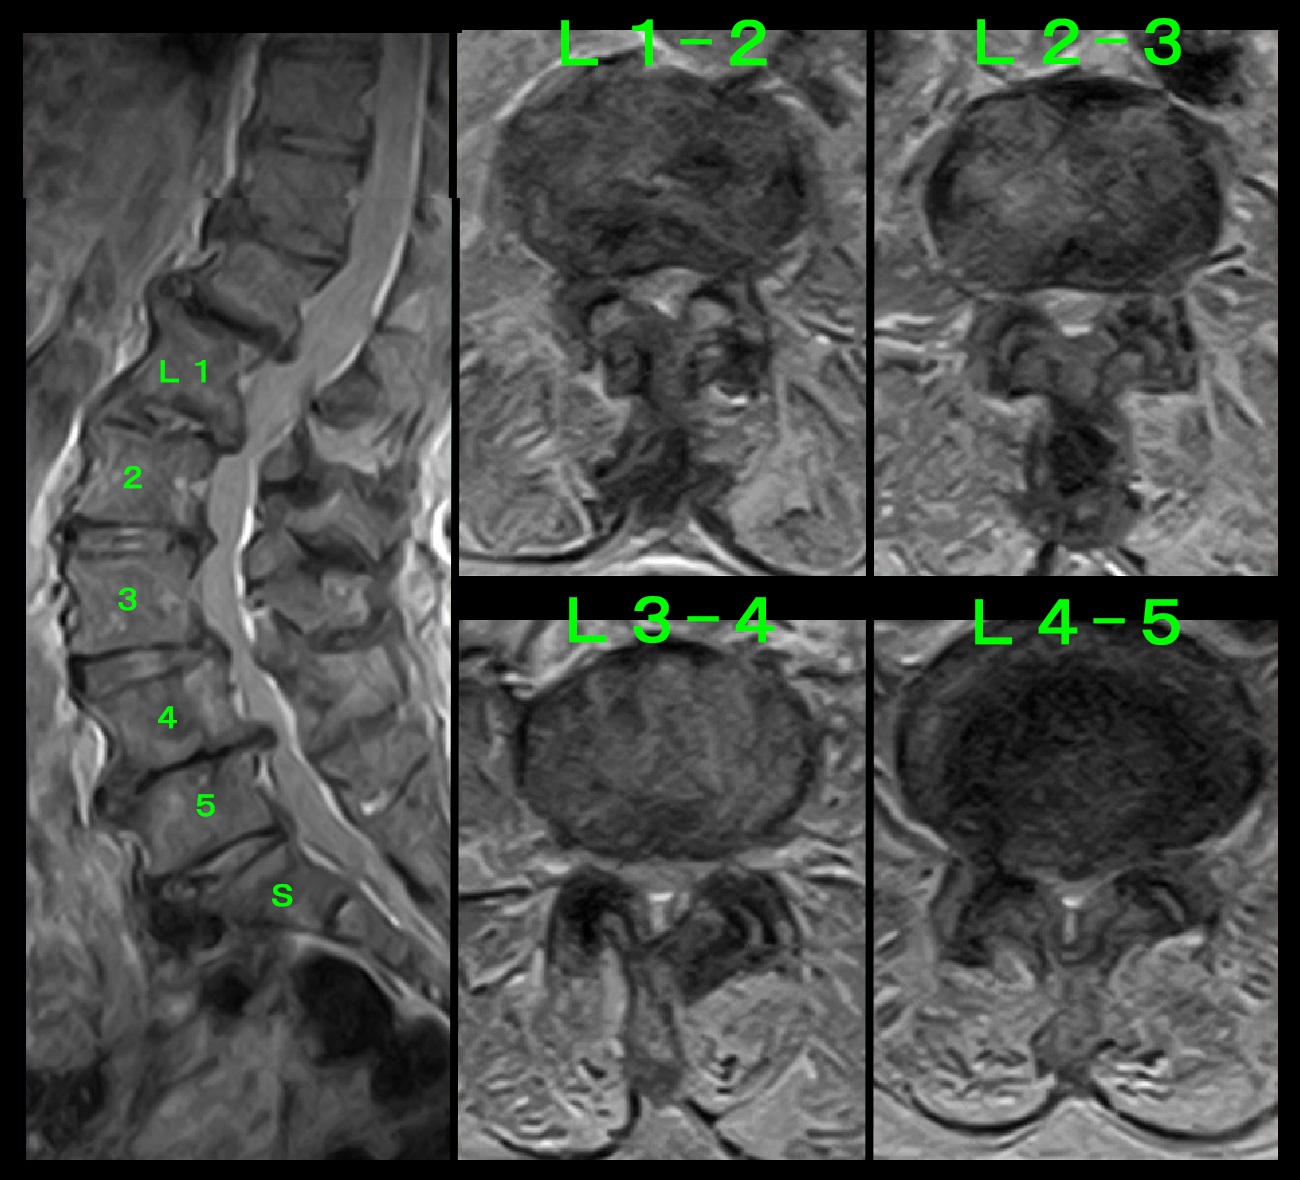

腰椎MR.jpg

腰椎MRI検査では、L12・L23・L34は中等度~重度の、L45は重度の脊柱管狭窄(脊髄が腰椎椎間板の老化により圧迫されている状態)が確認され、

私は、L5神経根ブロックで一定症状の軽減がえられる可能性があると診断しました。

まず、7月25日に左L5神経根ブロックを施行し、効果がえられれば右神経根ブロックも行いましょうと提案しました。

すると、8月2日には効果があったということで、右L5神経根ブロックも希望されました。